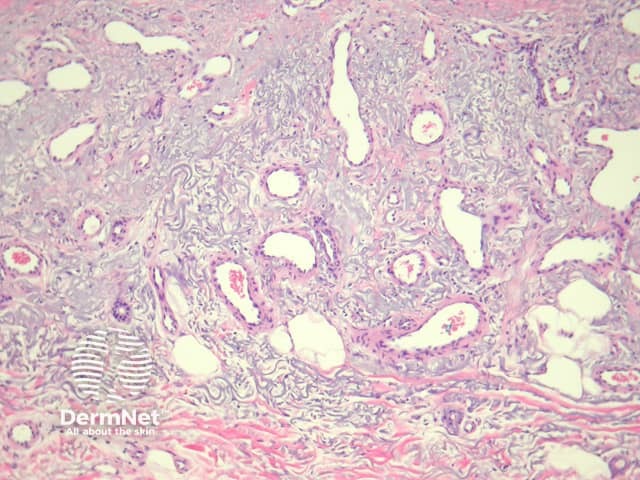

In acquired elastotic haemangioma, sections show prominent solar elastosis with a proliferation of dilated, fine endothelial-lined structures in the upper dermis forming a horizontal band (figure 1, 2). The deep margin of the proliferation is usually well defined. The endothelial lining is bland without multilayering or nuclear atypia (figure 3).

Figure 1

Figure 2